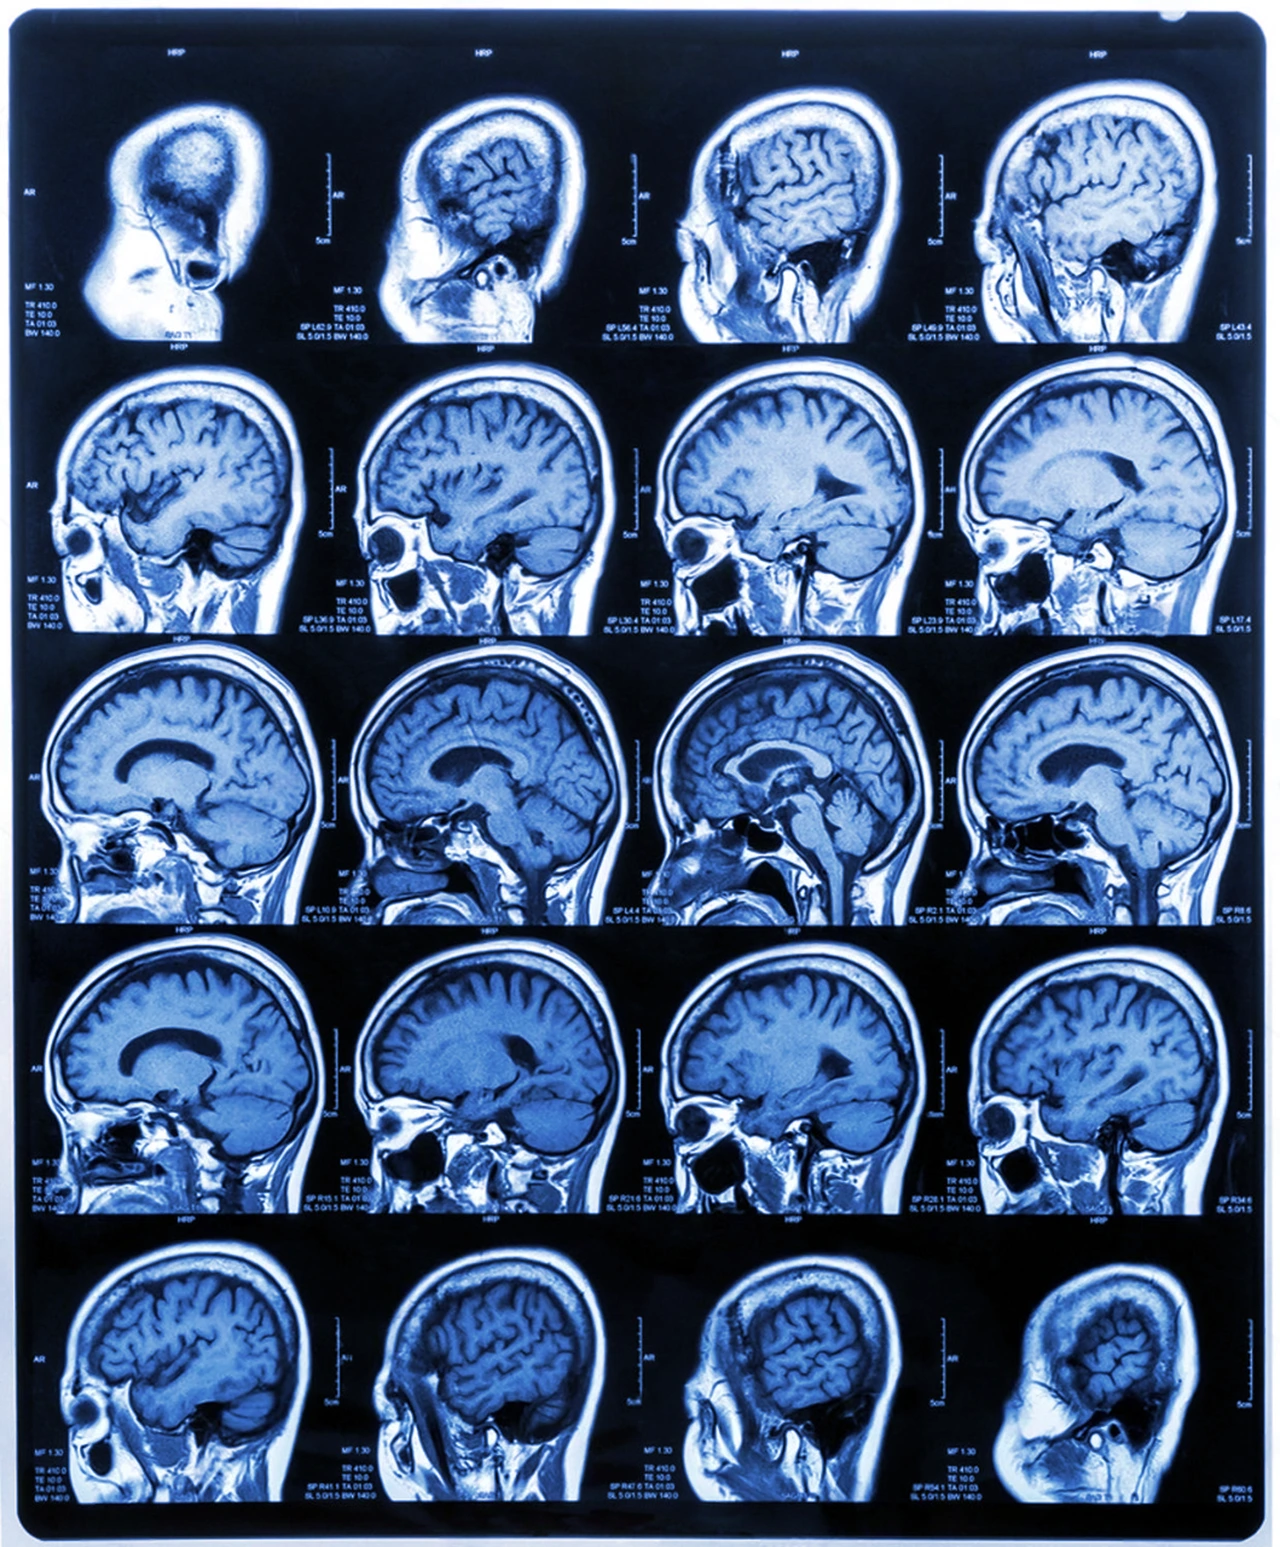

• Resonancia magnética (RM) y angiografía por RM: son útiles para observar el tejido cerebral y las arterias principales.

Resonancia magnética de vista lateral para diagnóstico de la enfermedad de Moyamoya.